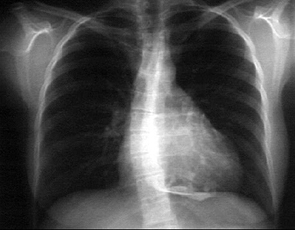

Labs - X Rays

Another Patient's

PA and Lateral

Click on the X rays to enlarge them.

Choose the best interpretation of the chest X rays:

Pericardial effusion

Normal

Lung mass and pericardial effusion

Pericardial calcification

Pericardial cyst